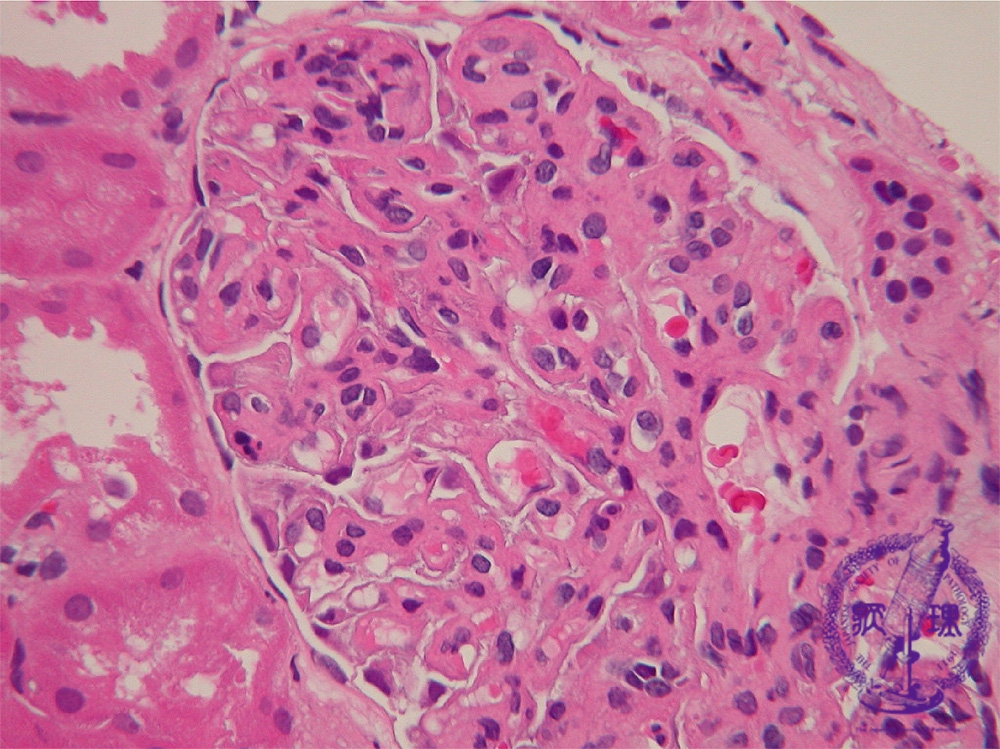

- ★(3)Membranoproliferative glomerulonephritis

Microscopic findings (HE, high power view): The capillary loops are thickened with proliferation of mesangial cells and matrix. Some glomerular loops appear lobulated (yellow dotted line, 10 to 13 o’clock)